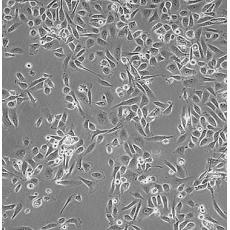

產品名稱 PC-3M

中文名稱 人前列腺癌細胞

組織來源 前列腺癌;骨髓轉移;男性

細胞種屬 Homo sapiens, human

生長特性 adherent

培養基 RPMI-1640+10% FBS+1% P/S

形態特征 epithelial

傳代方法 1:2-1:4